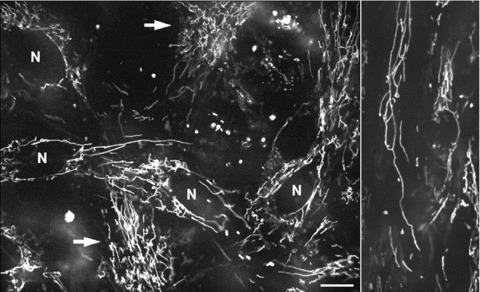

荧光共聚焦成像揭示人胰腺细胞中线粒体动力学的复杂模式。

Complex patterns of mitochondrial dynamics in human pancreatic cells revealed by fluorescent confocal imaging.

Mitochondrial morphology and intracellular organization are tightly controlled by the processes of mitochondrial fission-fusion. Moreover, mitochondrial movement and redistribution provide a local ATP supply at cellular sites of particular demands. Here we analysed mitochondrial dynamics in isolated primary human pancreatic cells. Using real time confocal microscopy and mitochondria-specific fluorescent probes tetramethylrhodamine methyl ester and MitoTracker Green we documented complex and novel patterns of spatial and temporal organization of mitochondria, mitochondrial morphology and motility. The most commonly observed types of mitochondrial dynamics were (i) fast fission and fusion; (ii) small oscillating movements of the mitochondrial network; (iii) larger movements, including filament extension, retraction, fast (0.1-0.3 mum/sec.) and frequent oscillating (back and forth) branching in the mitochondrial network; (iv) as well as combinations of these actions and (v) long-distance intracellular translocation of single spherical mitochondria or separated mitochondrial filaments with velocity up to 0.5 mum/sec. Moreover, we show here for the first time, a formation of unusual mitochondrial shapes like rings, loops, and astonishingly even knots created from one or more mitochondrial filaments. These data demonstrate the presence of extensive heterogeneity in mitochondrial morphology and dynamics in living cells under primary culture conditions. In summary, this study reports new patterns of morphological changes and dynamic motion of mitochondria in human pancreatic cells, suggesting an important role of integrations of mitochondria with other intracellular structures and systems.

线粒体的形态和细胞内组织是由线粒体分裂-融合过程紧密控制的。此外,线粒体的运动和再分布为细胞中特定需求部位提供局部 ATP 供应。在这里,我们分析了分离的原代人胰腺细胞中的线粒体动力学。使用实时共聚焦显微镜和线粒体特异性荧光探针四甲基罗丹明甲酯和 MitoTracker Green,我们记录了线粒体的时空组织、线粒体形态和运动的复杂和新颖模式。最常见的线粒体动力学类型是:(i)快速分裂和融合;(ii)线粒体网络的小振荡运动;(iii)较大的运动,包括丝状延伸、回缩、快速(0.1-0.3 μm/sec.)和频繁的振荡(前后)分支的线粒体网络;(iv)以及这些动作的组合;(v)单个球形线粒体或分离的线粒体丝状的长距离细胞内转运,速度高达 0.5 μm/sec。此外,我们在这里首次展示了线粒体形成不寻常的形状,如环、环和惊人的甚至结,由一个或多个线粒体丝状形成。这些数据表明,在原代培养条件下,活细胞中线粒体形态和动力学存在广泛的异质性。总之,这项研究报告了人胰腺细胞中线粒体形态和动态运动的新模式,表明线粒体与其他细胞内结构和系统的整合具有重要作用。